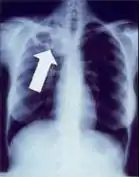

Tuberculosis creates cavities visible in x-rays like this one in the patient's right upper lobe.

In active pulmonary TB, infiltrates or consolidations and/or cavities are often seen in the upper lungs with or without mediastinal or hilar lymphadenopathy or pleural effusions ( tuberculous pleurisy). However, lesions may appear anywhere in the lungs. In disseminated TB a pattern of many tiny nodules throughout the lung fields is common - the so-called miliary TB. In HIV and other immunosuppressed persons, any abnormality may indicate TB or the chest X-ray may even appear entirely normal.

Abnormalities on chest radiographs may be suggestive of, but are not necessarily diagnostic of, TB. However, chest radiographs may be used to rule out the possibility of pulmonary TB in a person who has a positive reaction to the tuberculin skin test and no symptoms of the disease.

Cavitation or consolidation of the apexes of the upper lobes of the lung or the tree-in-bud sign[7] may be visible on an affected patient's chest X-ray.[1] The tree-in-bud sign may appear on the chest CTs of some patients affected by tuberculosis, but it is not specific to tuberculosis.[7]